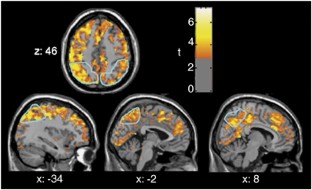

Changes in brain function during the initial weeks of abstinence from chronic methamphetamine abuse may substantially affect clinical outcome, but are not well understood. We used positron emission tomography with [F-18]fluorodeoxyglucose (FDG) to quantify regional cerebral glucose metabolism, an index of brain function, during performance of a vigilance task. A total of 10 methamphetamine-dependent subjects were tested after 5–9 days of abstinence, and after 4 additional weeks of supervised abstinence. A total of 12 healthy control subjects were tested at corresponding times. Global glucose metabolism increased between tests (P=0.01), more in methamphetamine-dependent (10.9%, P=0.02) than control subjects (1.9%, NS). Glucose metabolism did not change in subcortical regions of methamphetamine-dependent subjects, but increased in neocortex, with maximal increase (>20%) in parietal regions. Changes in reaction time and self-reports of negative affect varied more in methamphetamine-dependent than in control subjects, and correlated both with the increase in parietal glucose metabolism, and decrease in relative activity (after scaling to the global mean) in some regions. A robust relationship between change in self-reports of depressive symptoms and relative activity in the ventral striatum may have great relevance to treatment success because of the role of this region in drug abuse-related behaviors. Shifts in cortical–subcortical metabolic balance either reflect new processes that occur during early abstinence, or the unmasking of effects of chronic methamphetamine abuse that are obscured by suppression of cortical glucose metabolism that continues for at least 5–9 days after cessation of methamphetamine self-administration.